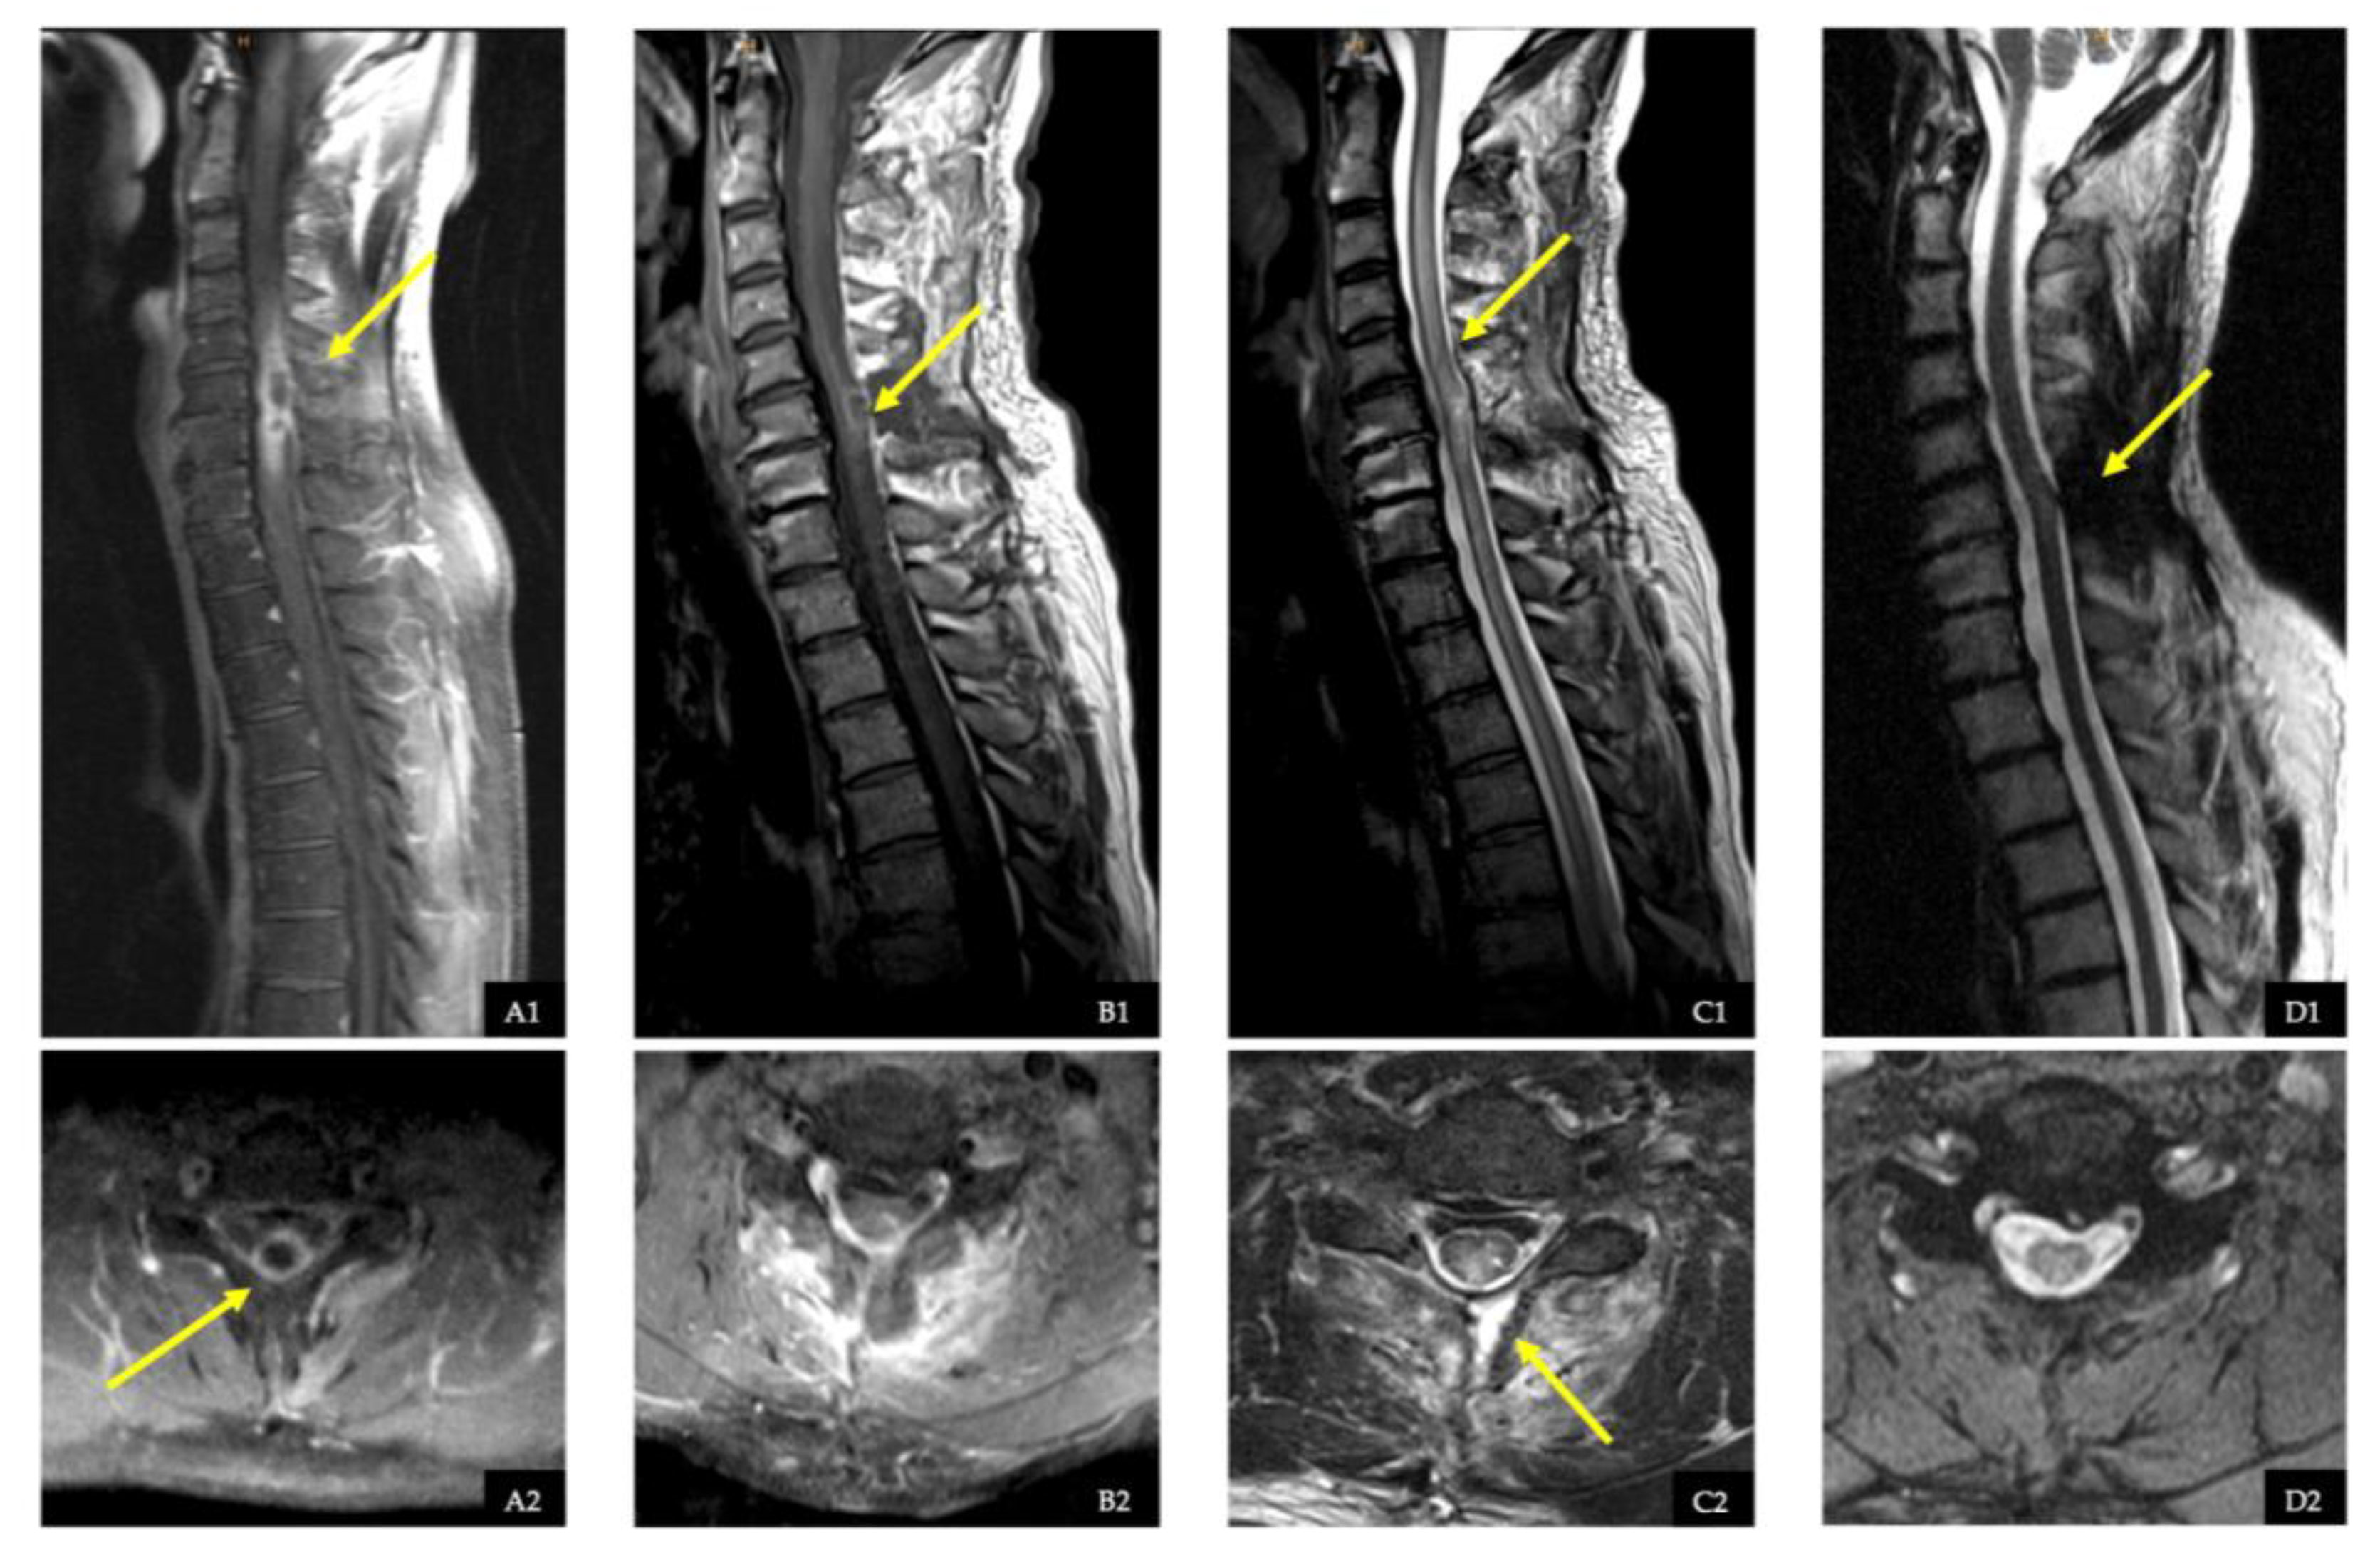

2.4. Illustrative Case with Spinal Intradural Abscess